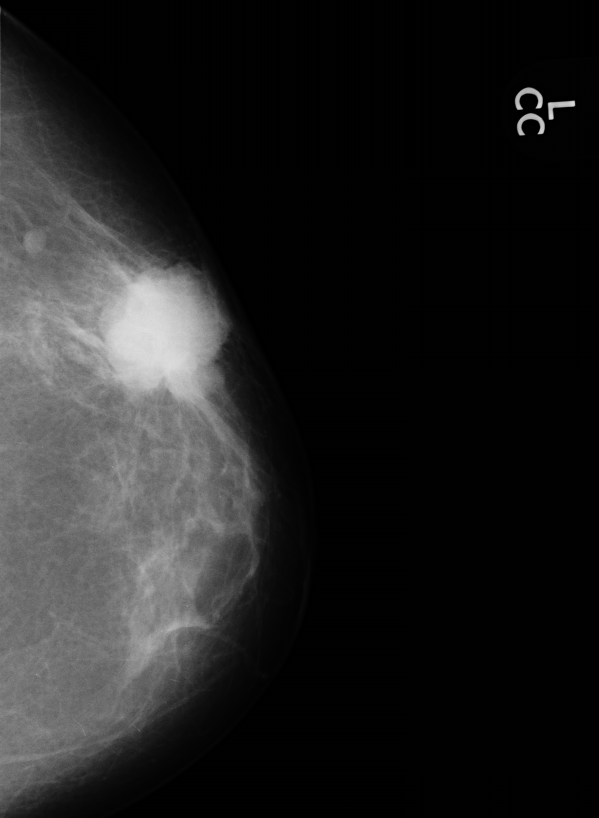

Маммография, это специализированное рентгенологическое исследование молочных желез, которое используется для раннего обнаружения опухолей, еще до появления внешних симптомов. Процедура выполняется с помощью специального аппарата — маммографа, который сжимает грудь, чтобы получить четкие изображения.

- Дигитальная маммография: обеспечивает более четкие изображения и возможность их цифровой обработки.

- Маммография с 3D-сканированием (томосинтез): позволяет получить объемное изображение молочной железы и заметно снижает число ложноположительных результатов.